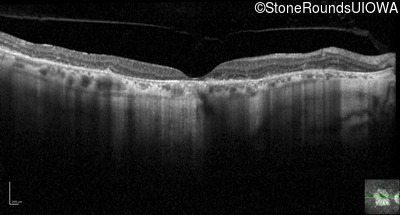

Optical Coherence Tomography - Right - 10/140

Exemplar / OCT Stack